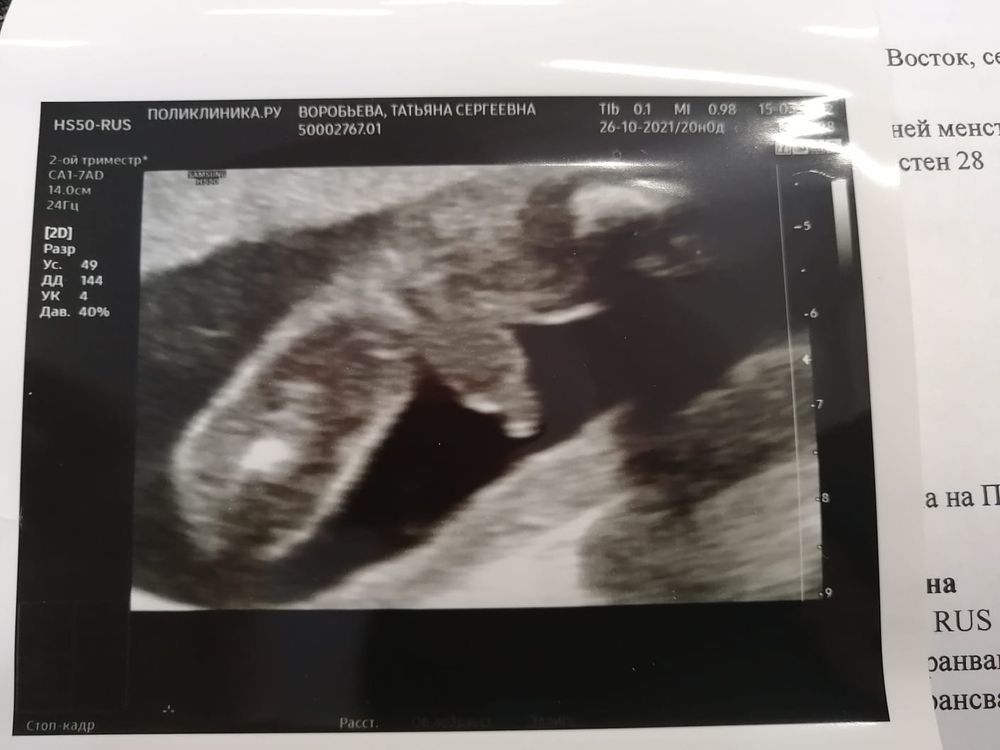

Пол малышаДевочки всем привет )Вам ошибались с полом ?Делала узи в 19 и 24 недели(разные врачи )по итогу девочка ,даже показали ,что между ног ничего нет .Вчера делала узи ,срок 28 недель и врач с уверенностью говорит,вот ваша мошонка и половой член,я в шоке естественно.И вот кому верить ?))

Tatyana, а мне в 24 недели тоже дали фотку ,плохо видно конечно )но обвели две полоски ,якобы половые губы )